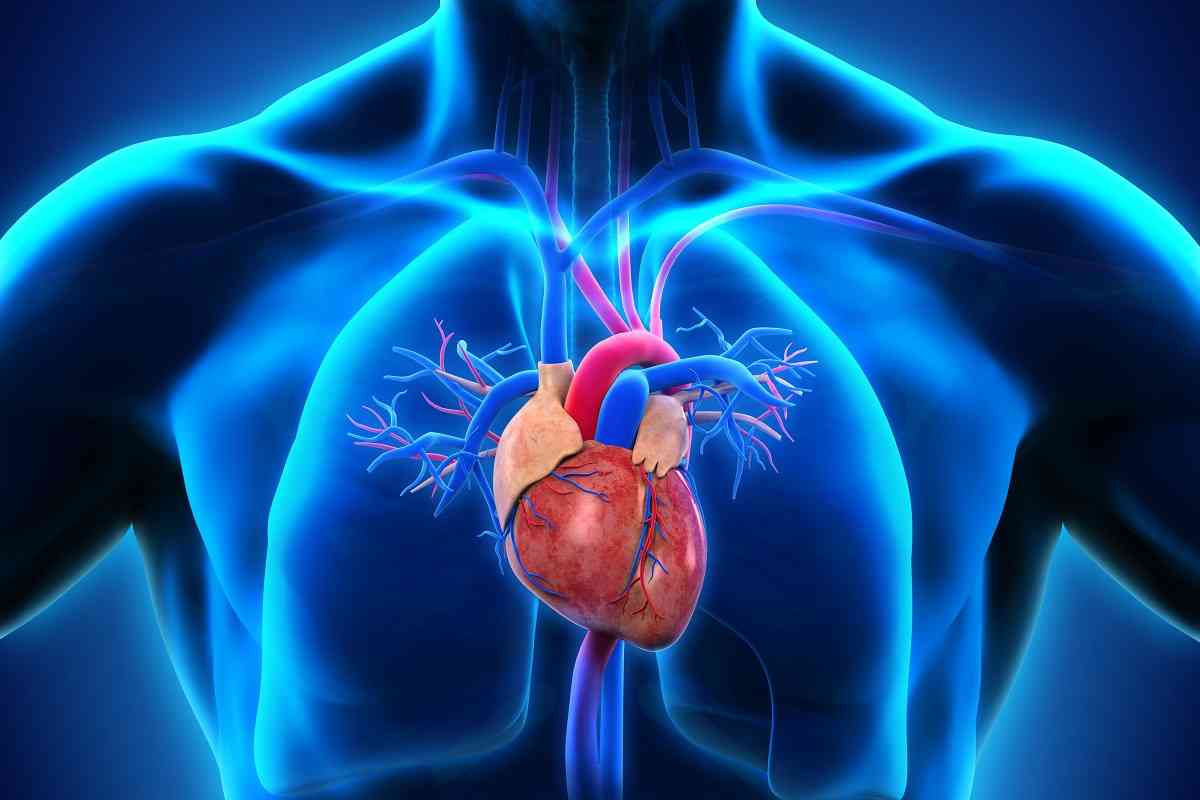

Τα ευρήματα όμως μιας μελέτης με περισσότερα από 100.000 άτομα, καταδεικνύουν ότι τα τεχνητά γλυκαντικά μπορεί να αυξάνουν τον κίνδυνο καρδιαγγειακής νόσου.

Η μελέτη διαπίστωσε ότι η καθημερινή πρόσληψη τεχνητών γλυκαντικών συσχετίστηκε με αυξημένο κίνδυνο καρδιαγγειακής νόσου συνολικά (αναλογία κινδύνου [HR] 1,09, 95% CI 1,01-1,18, p=0,03). Οι απόλυτοι αριθμοί επίπτωσης σε συχνούς καταναλωτές γλυκαντικών και μη καταναλωτές ήταν 346 και 314 ανά 100.000 ανθρωποέτη, αντίστοιχα.

Τα τεχνητά γλυκαντικά συσχετίστηκαν επίσης σημαντικά με αυξημένο κίνδυνο για αγγειακή εγκεφαλική νόσο (HR 1,18, 1,06-1,31, p =0,002), με ποσοστά επίπτωσης 195 και 150 ανά 100.000 ανθρωποέτη σε συχνούς καταναλωτές γλυκαντικών και μη καταναλωτές, αντίστοιχα.

Συγκεκριμένα, η καθημερινή πρόσληψη ακεσουλφάμης και σουκραλόζης συσχετίστηκε με 40% και 31% αυξημένο κίνδυνο στεφανιαίας νόσου, αντίστοιχα. Η πρόσληψη ασπαρτάμης συσχετίστηκε με 17% αυξημένο κίνδυνο για αγγειακά εγκεφαλικά επεισόδια.

Συμπερασματικά, τα ευρήματα αυτής της μεγάλης κλίμακας προοπτικής μελέτης υποδηλώνουν πιθανή άμεση συσχέτιση μεταξύ της συχνής κατανάλωσης τεχνητών γλυκαντικών, ειδικά ασπαρτάμης, ακεσουλφάμης, σουκραλόζης, και αυξημένου κινδύνου για καρδιαγγειακή νόσο. Συνεπώς, θα πρέπει να είμαστε προσεκτικοί και να τα χρησιμοποιούμε με μέτρο.